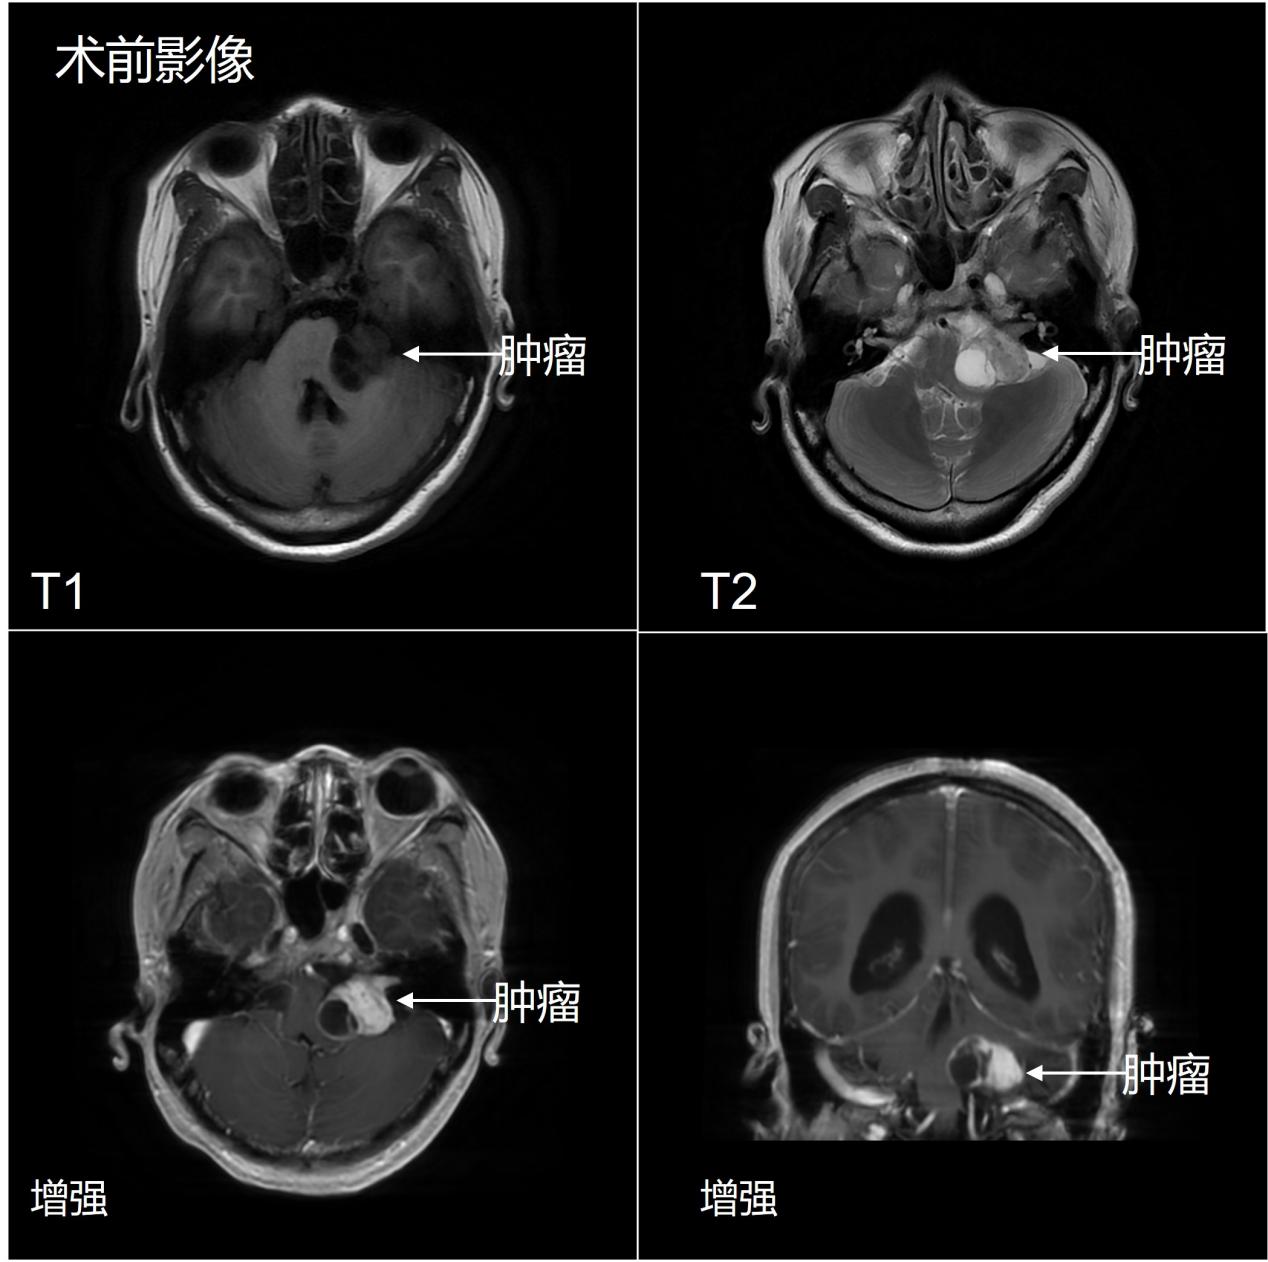

一位45岁女性因头晕、恶心、呕吐来院就诊,检查发现后颅窝肿瘤,考虑听神经瘤。听神经瘤为后颅窝最常见的良性肿瘤,一般起源于前庭听神经的前庭神经纤维。解剖上,面听神经在颅内相贴并行,因此,听神经瘤手术最常见的并发症为面听神经功能损伤,导致术后患侧面瘫和听力丧失。此患者肿瘤大,推挤压迫小脑和脑干,手术保留面听神经的难度较大。患者为年轻女性,因担心手术风险,术后面瘫,迟疑2月未入院,后因恶心呕吐症状加重决定手术治疗。

入院后,神经外科周乐教授、权俊杰副教授、马程文博士精心准备。在神经电生理监测技术辅助下,应用显微镜下神经束膜下分离技术,将肿瘤完全剥离切除,面听神经得到解剖保留。术后影像检查证实肿瘤完全切除。术后患者面部肌肉运动正常,同侧听力虽有下降,但仍有功能。目前患者已康复出院。